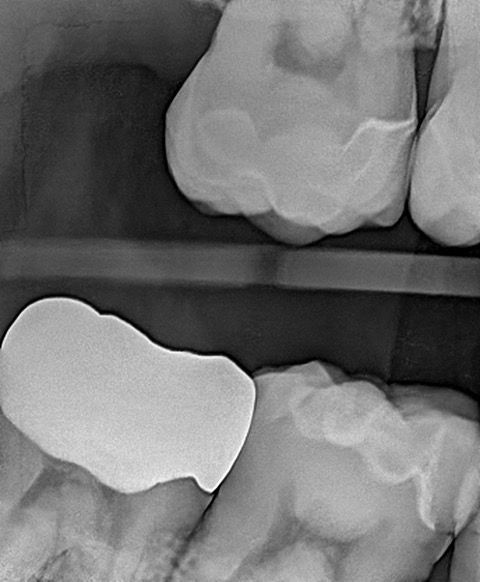

In my own practice, I compared two bitewings from the same patient, one taken with Acuity and one with our existing sensor, using identical exposure settings. The Acuity image immediately stood out. It showed noticeably sharper definition, cleaner contrast, and clearer interproximal visibility. The improvement was visible at a glance and reinforced the diagnostic advantages reported by our evaluators. This kind of image sharpness saves time and reduces retakes.